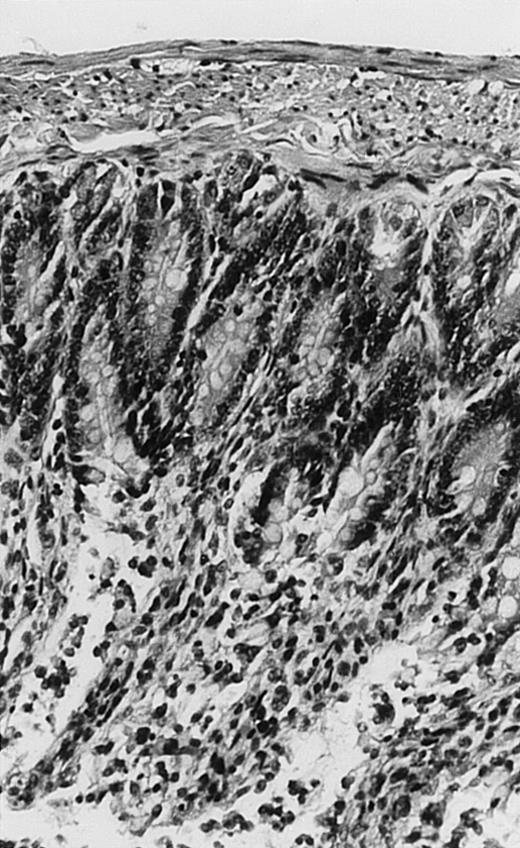

Pathologic findings in the small and large intestine were strikingly different depending on the treatment group. Figure 2A shows a representative pathologic sample from an animal assigned to the control group. Marked thinning of the bowel wall and extensive areas of epithelial cell sloughing was noted. Animals randomized to rhG-CSF treatment had minimal improvement in histologic findings with focal regions of preserved epithelium (Fig2B). Animals randomized to the rhIL-11 group showed substantial improvement with thickening of the epithelial layer and preservation of mucosal cell integrity (Fig 2C). Animals receiving both rhG-CSF and rhIL-11 had the most favorable histologic findings with normal mucosal thickness, minimal inflammatory changes, and preserved tissue architecture (Fig 2D). The composite analysis of the gastrointestinal pathology is provided in Table 1.

Histopathology of small intestinal mucosa cut in transection from an animal in each treatment group (study day 8). The upper panel (row 1) is a low power view (original magnification × 57); the lower panel (row 2) is a high power view (original magnification × 144). Note the diffuse thinning and necrosis of the mucosa with sloughing of intestinal epithelial cells in the control animal (A). There is progressive recovery of the thickness of the mucosa, reduction in inflammatory changes, and improved epithelial architecture with rhG-CSF (B), rhIL-11 (C), and combination therapy with rhG-CSF+IL-11 (D).

rhIL-11 has been shown to have marked effects on gastrointestinal epithelial surfaces. rhIL-11 blocks apoptosis of epithelial cells exposed to radiation and chemotherapy in mice.22 rhIL-11 is protective in a variety of mucositis models and in models of intestinal inflammation.4,23,24 rhIL-11 has been shown to prolong the G-0 phase of growth of intestinal epithelial cells. The precise mechanism of action is not known, but it has been observed that rhIL-11 decreased pRB (retinoblastoma protein) phosphorylation (an important signaling event in cell cycling) within intestinal epithelial cells.32 rhIL-11 has protective effects on gastrointestinal mucosa in transgenic rats, which possess HLA-B27 antigens.4These animals develop an inflammatory colitis that is similar in many respects to human inflammatory bowel disease. rhIL-11 treatment in these animals decreases intestinal inflammation and chronic diarrhea. Based on these preclinical findings, rhIL-11 is currently in clinical trials in both inflammatory bowel disease and chemotherapy-induced mucositis.33 The remarkable capacity of rhIL-11 to protect the gastrointestinal mucosal integrity after chemotherapy is apparent in the current series of experiments (Fig 2).